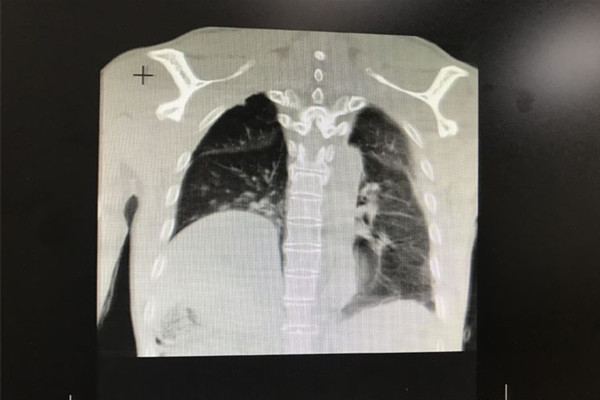

患者李某,在工作时不慎被搅拌机绞压胸腹部及左上肢,急诊转入我院时,颜面部青紫,上半身遍布出血点,左侧胸廓塌陷,反常呼吸明显,右侧呼吸音明显减弱,腹部压痛明显,左上肢严重毁损,情况十分危急。急诊科医护人员立即开通绿色通道,快速完成CT检查,实施紧急救治,并通知胸心外科和麻醉科及辅助科室做好抢救准备。结果提示,患者左侧多根多处肋骨骨折、左侧胸腔积液、右侧膈疝、脾脏破裂,肝脏挫伤,左上肢粉碎性骨折。

患者胸腹部挤压伤并创伤性窒息,病情极其危重,随时都会有生命危险,容不得半点耽搁。在对患者病情与手术方案进行细致的讨论后,由我院胸外科、创伤骨科、普外科、手麻科等科室专家组成的医疗团队立即对患者进行急诊手术抢救。胸外组经胸腔镜辅助行双侧胸腔探查见左侧4-12肋骨骨折,其中4-10肋骨成粉碎性骨折,左肺下叶广泛挫裂伤,胸腔积血2000余毫升,双侧膈肌破裂、肝脏完全疝入右侧胸腔。普外组探查腹腔积血1000余毫升、脾脏破裂。创伤骨科组探查见左上肢粉碎性骨折,软组织毁损严重,在多学科协作下成功完成左侧血胸清除、肺修补、左侧膈肌修补、左侧肋骨骨折复位内固定术等手术。各学科争分夺秒,配合默契,凭借着娴熟的医疗技术和丰富的临床经验,让奄奄一息的患者重获新生。